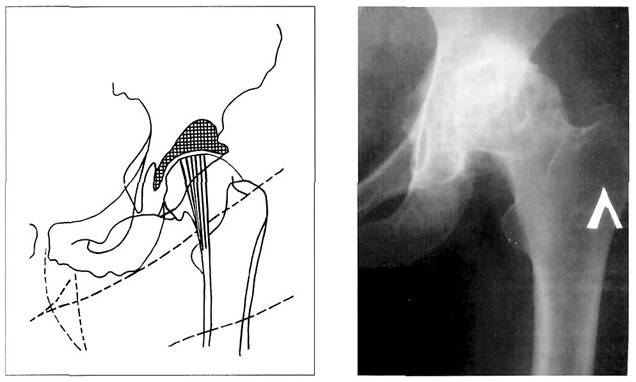

На рисунках 1 и 2 представлены нормальные соотношения между головкой бедренной кости и вертлужной впадиной в прямой и боковой проекциях. Головка бедренной кости проецируется кнутри от перпендикуляра, опущенного от края вертлужной впадины. Если перпендикуляр пересекает головку, то можно предположить наличие ее недопокрытия вследствие ацетабулярной дисплазии.

Рис. 1. Схема рентгенограммы здорового тазобедренного сустава: 1 - «фигура слезы»; 2 - ямка вертлужной впадины; 3 - крыша вертлужной впадины; 4 - передний и 5 - задний края вертлужной впадины; 6 - «фигура полумесяца» (дно седалищно-суставной борозды); 7 - головка бедра; 8 - рентгеновская суставная щель тазобедренного сустава; 9 - шейка бедра; 10 - большой вертел; 11 - малый вертел; 12 - запирательное отверстие; 13 - межвертельный гребень; 14 - передненижняя ость подвздошной кости; 15 - вертельная ямка; 16 - симфиз; 17 - верхнепередняя ость подвздошной кости; 18 - медиальная ость; 19 - латеральная поверхность бедра; 20 - седалищный бугор; 21 - апофиз седалищного бугра; 22 - линия Шентона; 23 - апофиз гребня подвздошной кости (из руководства Майковой-Строгановой B.C., Рохлина Д.Г., 1957).

Рис. 2. Схема боковой рентгенограммы тазобедренного сустава: 1 - симфиз; 2 - шейка бедра; 3 - головка бедра; 3 а - рентгеновская суставная щель; 4 - седалищный бугор; 5 - малый вертел; 6 - задняя поверхность бедренной кости; 7 - большой вертел; 8 - передняя поверхность бедренной кости (из руководства Майковой- Строгановой B.C., Рохлина Д.Г., 1957).

Существуют три качественных признака, характеризующих на рентгенограммах у взрослых нормальные соотношения между головкой бедренной кости и суставной впадиной в тазобедренном суставе: а) головка бедренной кости располагается кнутри от перпендикуляра, опущенного от наружного края вертлужной впадины; б) линия Шентона, проводимая по внутреннему краю шейки бедренной кости к верхнему краю запирательного отверстия, дугообразна; в) «фигура полумесяца» проекционно накладывается на нижнемедиальный квадрант головки бедра. Кроме того, существуют количественные показатели рентгеноанатомических взаимоотношений в тазобедренном суставе, характеризующие его стабильность (рис. 4):